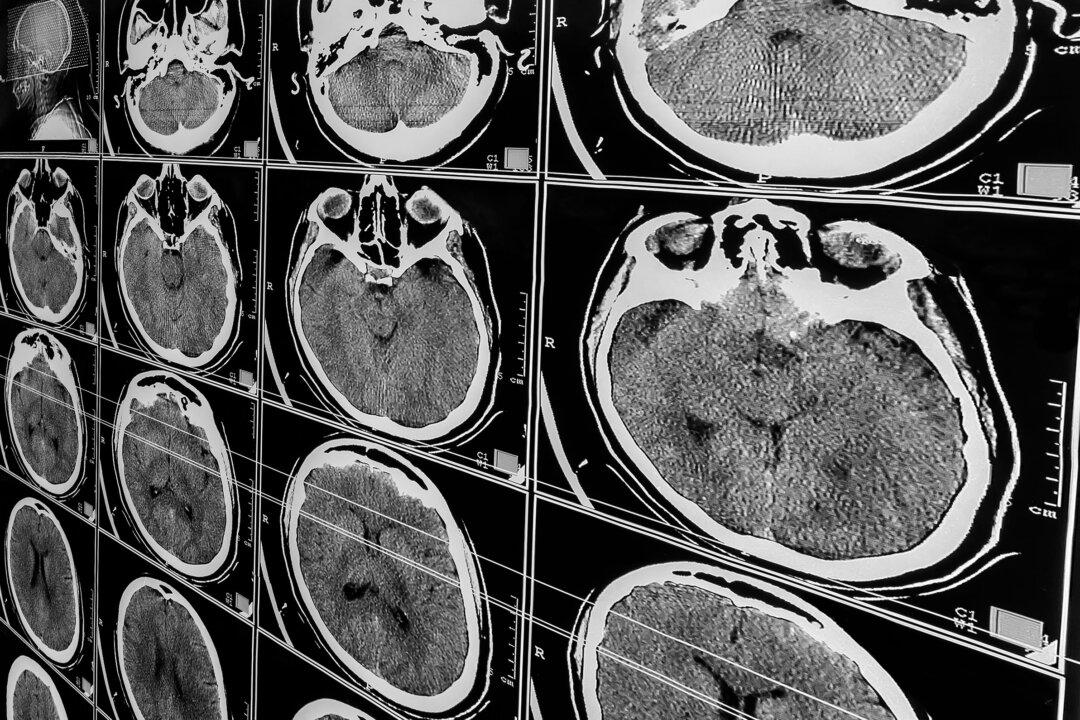

People Near Death From Traumatic Brain Injury May Still Revive: Study

Advanced imaging can detect covert consciousness, offering hope for seemingly hopeless cases, experts say.

The detection of “covert consciousness” through advanced neuroimaging has “fueled a message of hope,” Dr. Dams-O'Connor told The Epoch Times. This sort of imaging can find indicators in the brain that are not detected by clinical evaluations and may have significant prognostic value. Some people who appear to have little hope of recovery may possess covert consciousness, which is associated with improved outcomes.